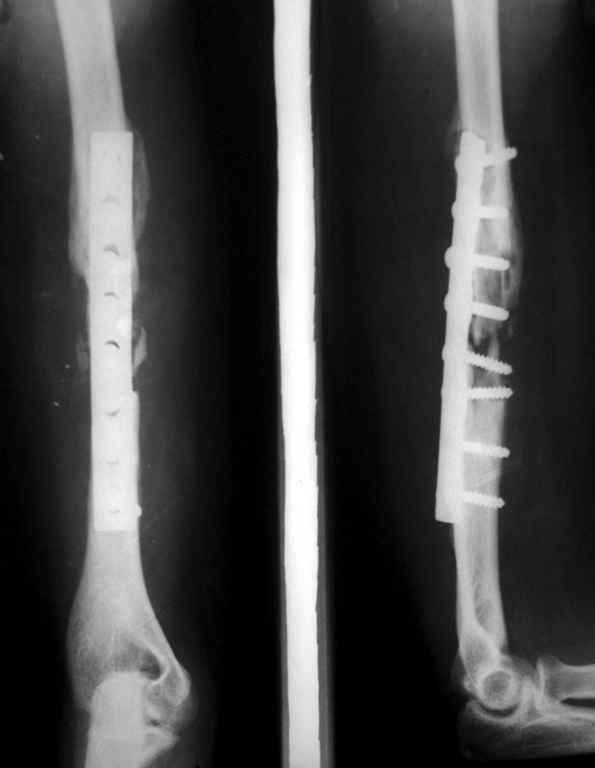

был ли остеосинтез с диастазом - неизвестно, но неадекватность фиксации пластиной достаточно очевидна.

1 пластина тонкая

2 всего 6 шурупов через пластину - для плеча это минимальное требование при свежем переломе

3 проксимальный фрагмент на момент ( или в ходе) второй операции был расколот , о чем свидетельствует наиболее проксимальный lag screw, то есть прокс 3 шурупа через пластину были введены в расколотый фрагмент. Неудивительно, что пластину вырвало

Здравствуйте Владимир! На всех рентгенограммах определяется лизис костной ткани вокруг шурупов, на боковой проекции похоже секвестр, это -- в пользу остеомиелита. Рекомендую: удаление металлоконструкций краевую резекцию концов плечевой кости, ревизию каналов после удаленных шурупов, при наличии признаков остеомиелитических грануляций провести кюретаж. Наложить спице-стержневой АВФ + открытую репозицию отломков. При необходимости проточно- промывное дренирование. Желательно применение Коллапана интраоперационно.